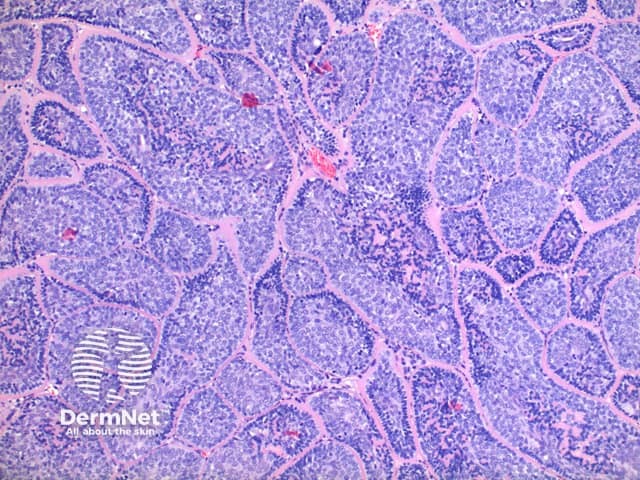

Low power view of cylindroma shows a non-encapsulated tumour nodule arising from the dermis (Figure 1). This is formed by multiple irregular tumour islands, distributed in an aptly named ‘jigsaw’ pattern (Figure 2). Surrounding the tumour islands, and in discrete droplets within the nodules is a thick hyaline deposit (Figure 3). Two populations of cells are noted to make up the tumour nodules. A smaller cell with a hyperchromatic nucleus tending to the periphery, and larger cells with open nuclei throughout the centre of the nodules (Figure 4).

Figure 2